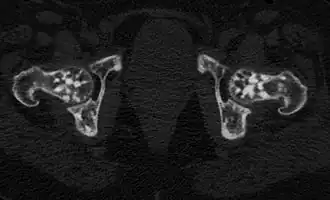

![]() Проявления остеопойкилии в костях таза и головках бедренных костей (компьютерная томограмма). | |

Остеопойкилия (остеопойкилоз, остеопатия врождённая пятнистая множественная, остеопатия врождённая рассеянная склерозирующая) — редкое наследственное заболевание костной ткани, проявляющееся в негомогенности, «пятнистости» её окостенения.

Заболевание является системным, проявляется очагами остеосклероза округлой и овальной формы, как правило приблизительно одинакового калибра, от 2 мм до 20 мм. Очаги могут располагаться практически во всех костях, однако наиболее часто выявляются в коротких костях запястья и предплюсны, метафизах и эпифизах длинных трубчатых костей (плечевых, бедренных) при интактности их диафизов[6].